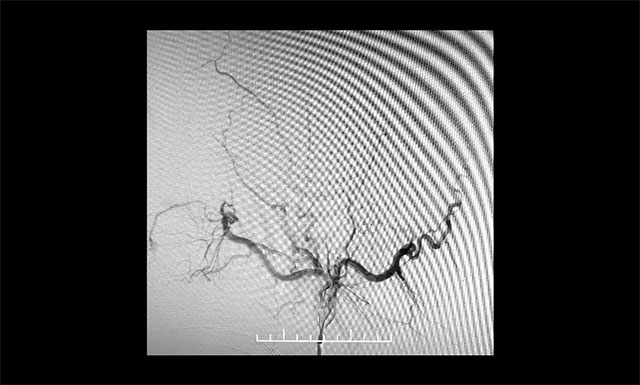

▲ 术毕左侧颈外动脉造影